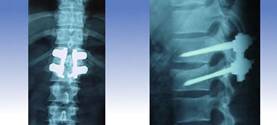

Corresponde a la fijación o estabilización mediante elementos de titanio que unen una vértebra con otra, provocando una fusión cuando se combina con el aporte de injerto óseo actualmente aportados, habitualmente en forma de biomateriales lo que implica no tener que sacar el injerto de la cadera o cresta iliaca.

Con esto se consigue la llamada fijación o estabilización (fusión o artrodesis), que es usada fundamentalmente para los problemas degenerativos (desgaste) de la columna lumbar o cervical.

También las estabilizaciones de columna se pueden realizar mediante cages (cajas de titanio), colocadas habitualmente por vía anterior en la columna cervical y en la columna lumbar puede ser aplicada por ambas vías, es decir, anterior y posterior.